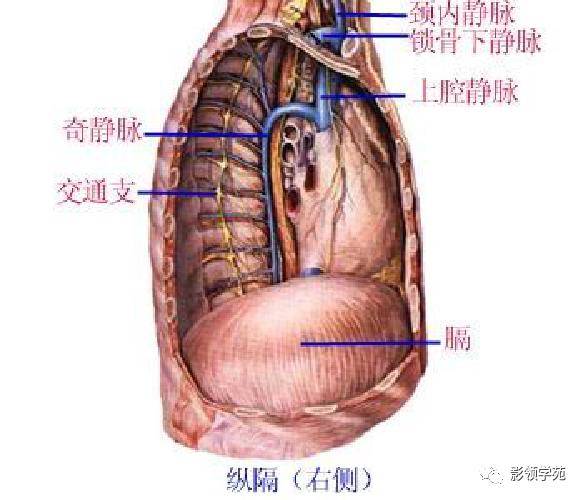

心血管系统

心血管系统